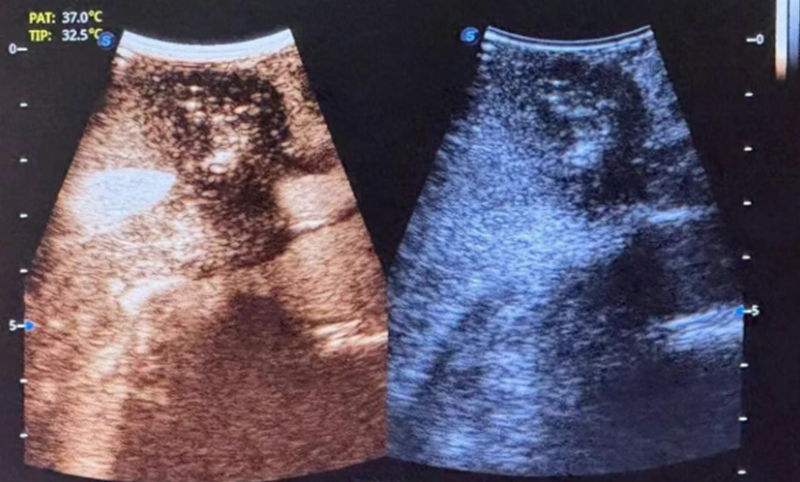

术后超声造影显示肿瘤部位呈无血供现象,周边血管结构保存完整,消融效果良好且安全。消融完成后,术者退出电极针,手术顺利结束,术后给予对症支持治疗,患者恢复良好。

术后即刻造影▲